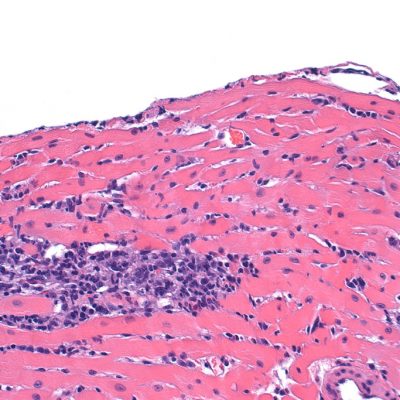

Propias células inmunes del corazón puede ayudar a sanar: Estudio